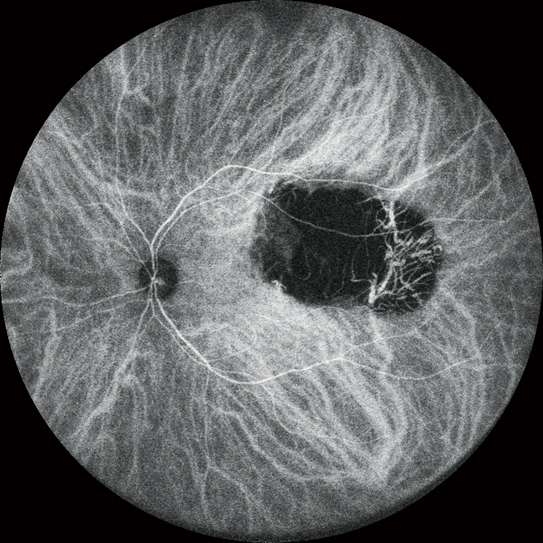

高清動態血管造影

可錄制分辨率高達1,024 x 1,024像素,最長時長為120秒的視頻。在同一次測量中也可分段錄制多個短視頻。

FA和ICG同步血管造影

Mirante操作簡便,可同步拍攝FA和ICG影像。實時IR監測方便操作者在熒光產生前調整拍攝位置,降低錯過血管造影早期階段的風險。

自動增益控制(AGC)可同步調整各個FA和ICG圖像的對比度,使動態血流成像成為一個非常簡便的過程。